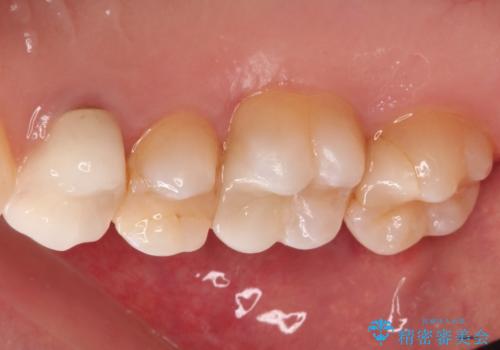

【VPT(歯髄温存療法)とセラミックインレー】深い虫歯でも神経を残したい

- 虫歯が大きく神経まで達していたので、VPT(歯髄温存療法)を行って細菌感染した部分の神経のみ取り除き、保存可能な神経は保存し被せ物はセラミックインレーで治療を行いました。

- 121,000円(VPT:44,000円 セラミックインレー:77,000円)費用は治療当時の料金となります